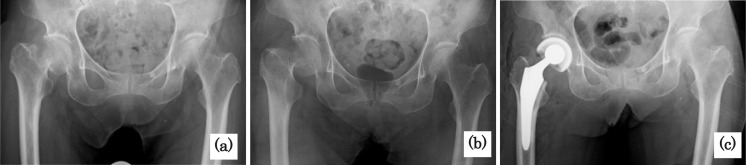

[Purpose] We report the case of an 81-year-old woman with a femoral neck fracture whose gait function improved with in-hospital physical therapy prior to surgery. [Participants and Methods] The patient's planned bipolar hip arthroplasty was postponed due to suspected metal allergy, and she commenced rehabilitation on hospital day 4. [Results] On day 7, the patient stood and was transferred with assistance. Subsequently, owing to pain, she only left her bed during rehabilitation. On day 10, the fracture was externally fixed using a soft-conforming lumbar immobilization orthosis, which relieved the pain. The patient was allowed to stand and was transferred under supervision. On day 22, surgery was scheduled after obtaining a negative metal patch test result. On day 23, the patient was able to walk 25 m using a walker. Bipolar hip arthroplasty was performed on day 28. On day 30, she walked 10 m using a walker with light assistance. On day 52, the patient walked independently using a cane. The patient was discharged on day 63. [Conclusion] External lumbar immobilization bandages effectively reduced motion-related fracture pain. The high frequency of rehabilitation while waiting for surgery effectively prevented perioperative complications and promoted early postoperative walking recovery.